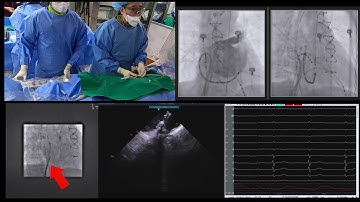

ECHO Guidance for Watchman Device- TEE Views for LAA sizing, Trans-septal Puncture and Implantation